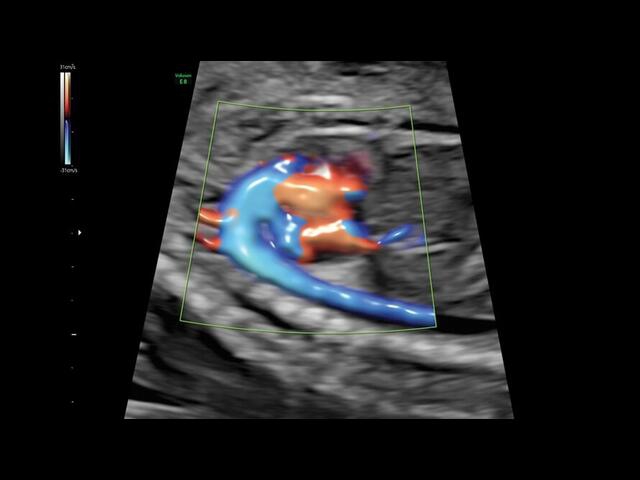

Система GE Voluson E8 обладает значительной вычислительной мощностью, которая позволяет решать даже самые сложные задачи в области диагностики плода. Она отличается высоким уровнем качества и статусом, предоставляя врачу потрясающие изображения во время 2D/3D-исследований. Кроме того, система всегда готова к использованию режима 4D благодаря чувствительному цветному доплеру.

• HDlive: Технология HDlive обеспечивает анатомический реализм и высокую точность диагностики, позволяя совмещать несколько независимых источников света для создания оттенков и теней.

• HD-FlowTM для точного изучения кровотока и прорисовки сосудов.